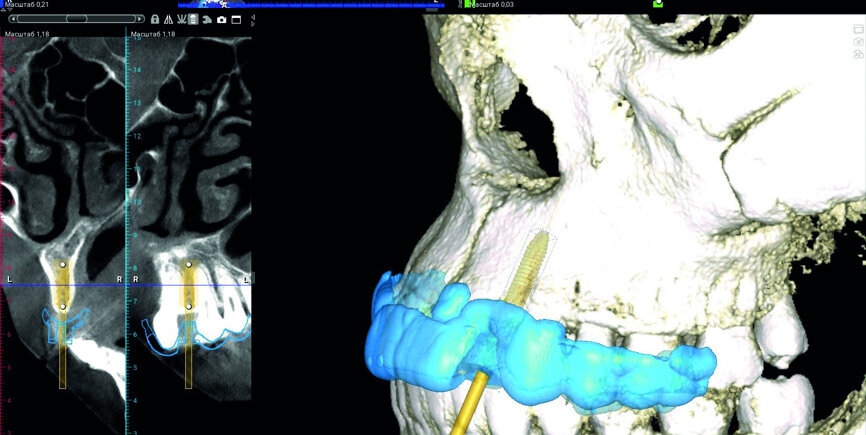

Fig. 3: Digital implant and surgical guide planning in Planmeca Romexis software.

Fig. 4: Digital implant and surgical guide planning in Planmeca Romexis software.

In this particular case, we started with an aesthetic analysis of the patient’s CBCT data and concluded that a Straumann implant with a 2.9 mm diameter would fit in the area of tooth 22, if we used a surgical guide for maximum precision (Figs. 3–5). For tooth #12, we decided to fabricate a thin-walled IPS e.max ceramic restoration (Ivoclar Vivadent).